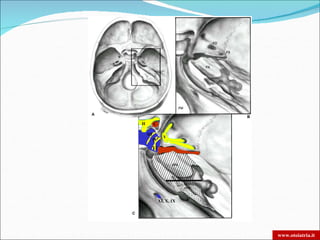

SKULL BASE

FORO LACERO

ANTERIORE

FORO OVALE

CANALE

CAROTIDEO

FORO SPINOSO

FORAME

GIUGULARE

CANALE DEL N.

FACCIALE

II         C

III

V

IV

VI

XI, X, IX

SKULL BASE FORO LACERO ANTERIORE FORO OVALE CANALE CAROTIDEO FORO SPINOSO FORAME GIUGULARE CANALE DEL N. FACCIALE www.otoiatria.it

II C III V IV VI XI, X, IX www.otoiatria.it